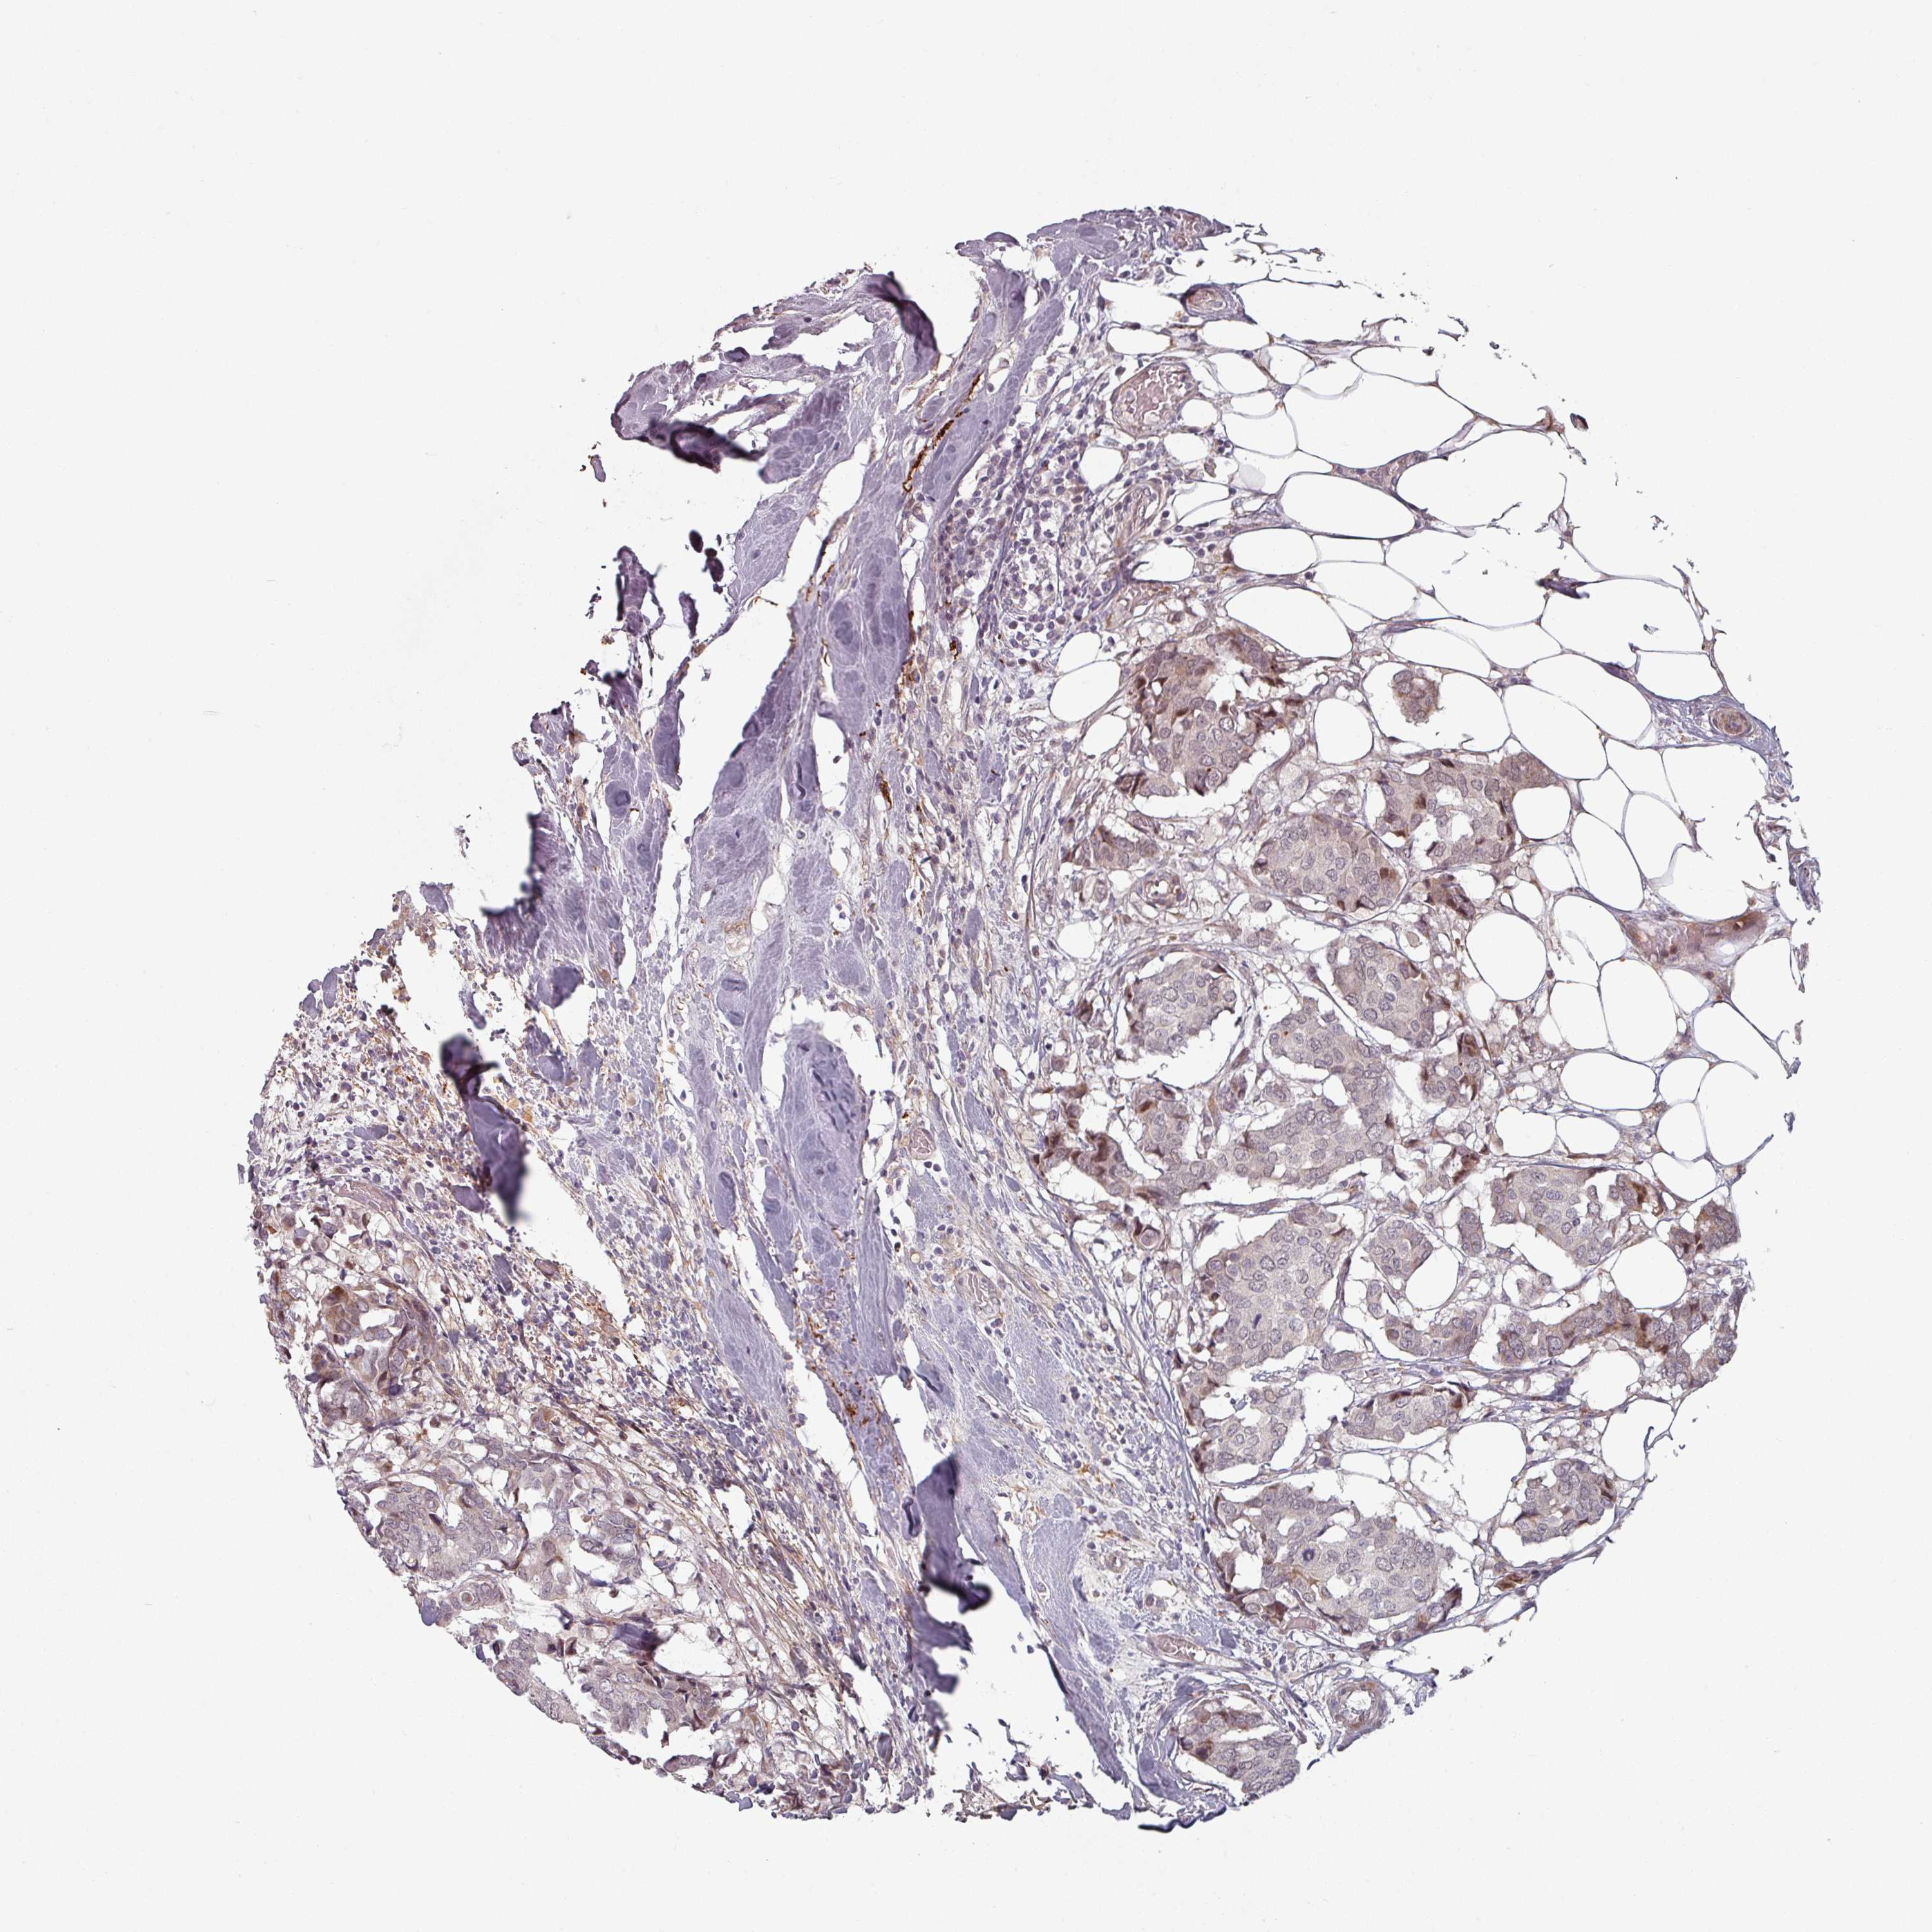

BRCA TCGA BRCA VALIDATION PROTEIN EXPRESSION

ANTIBODIES

AND

VALIDATION